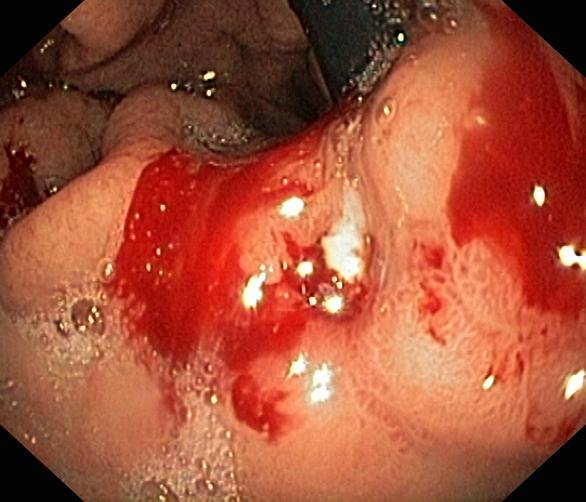

Krwawienie